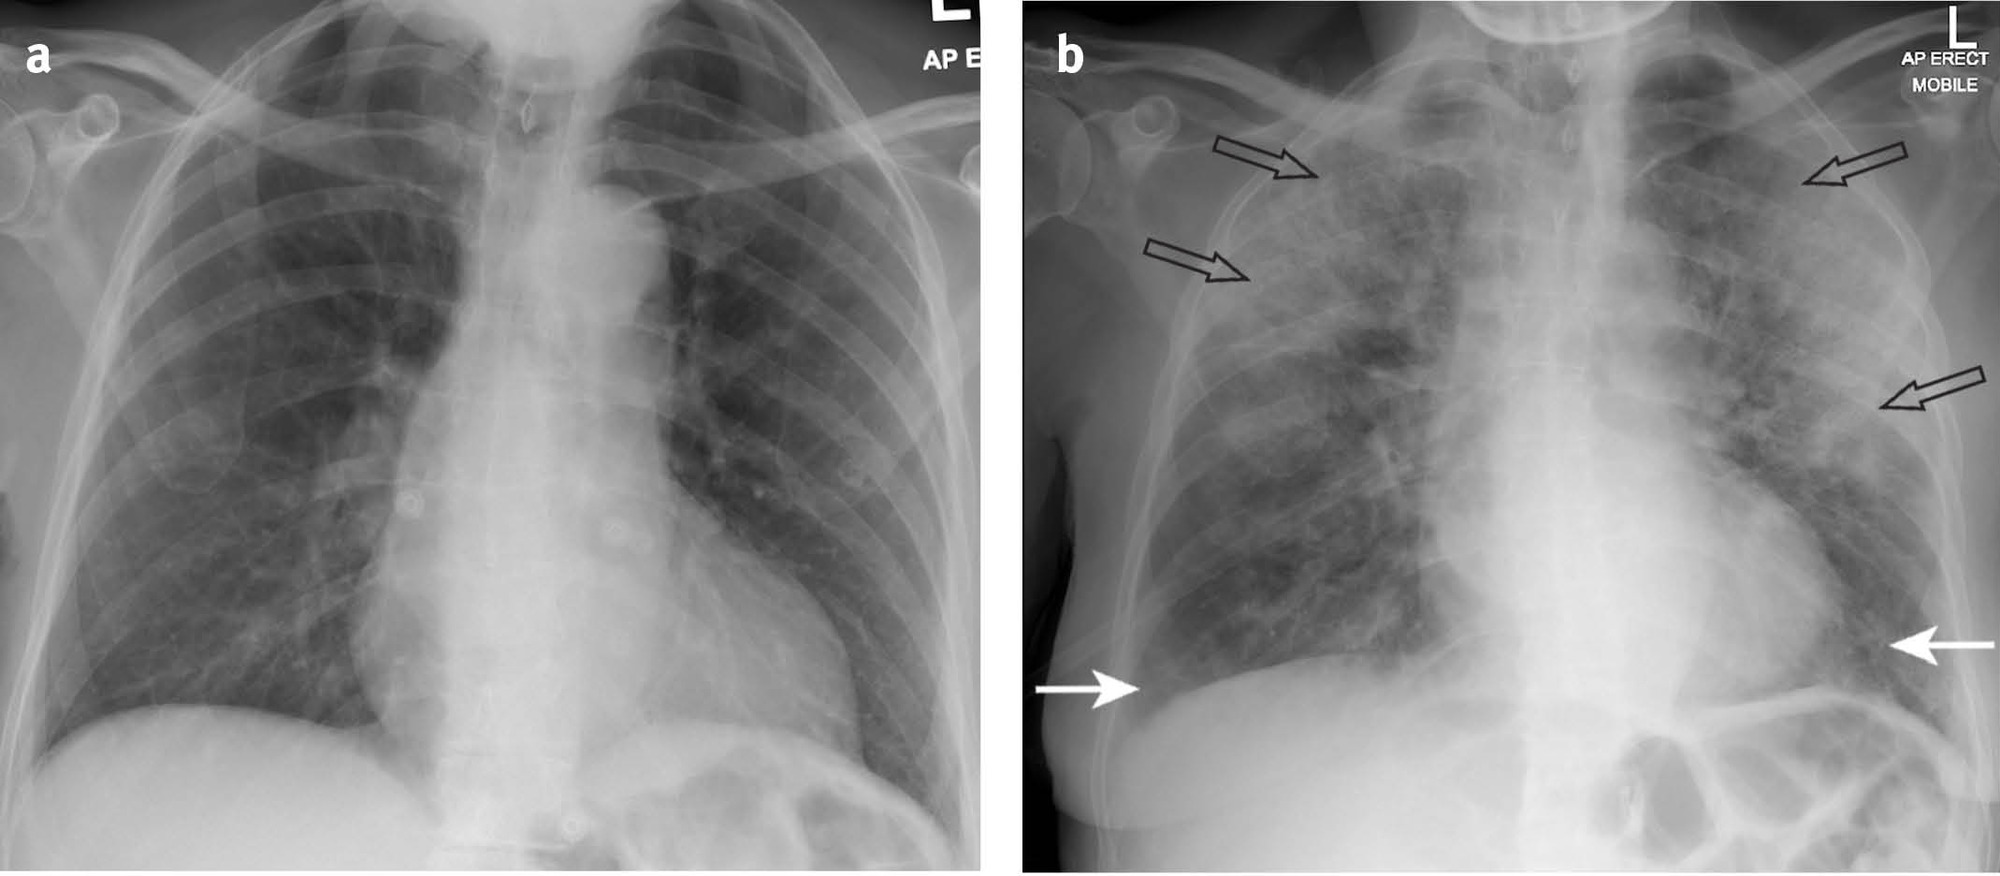

- AP view: 심장이 확대되어 보이며, 견갑골에 의해 폐야가 많이 가려지며, 횡경(Diaphragm)막이 높이 올라가 있어 폐가 좁게 나타남

- 따라서 COVID-19 선별진료소와 같이 Chest AP에서 얻은 CXR 이미지는 폐 병변을 보기에는 사실 썩 좋지 않은 경우가 꽤 있다. (Dataset 수집할 때 이러한 부분도 고려하면 좋을 듯)

- 위의 그림을 보면 같은 환자인데 Chest AP에서는 심장 size도 크고 그리고 견갑골에 의해서 폐야도 많이 가려지는 형태고 그 다음에 diaphragm도 많이 올라와 있기 때문에 PA와 비교했을 때 상당히 폐야가 좁고, 굉장히 내부의 vessel도 굉장히 engorgement(폐에서의 염증성 충혈)되어 보이는 경우가 많습니다.

- 이러한 경우, GGO 병변을 딱히 구분할 수 없거나 잘 안보이는 경우가 생길 수 도 있습니다. → 참고로 GGO는 COVID-19에서 발견되는 주요 소견 중 하나입니다.

- 또한, Chest X-ray는 누워서 찍기보단 서서 찍는 것이 좋습니다.

- 아래의 환자는 effusion이 있던 환자인데, chest AP 를 누워서 찍으니까 effusion이 전부 뒤로 깔려서 폐 병변을 보기가 상당히 어렵게 됐습니다. 가끔 chest X-ray 데이터셋을 보면 저런 경우를 종종 볼 수 있는데 이런 경우 effusion이 있는 환자가 누워서 찍은건 아닌지 고려한 후 데이터셋을 제거하는 것이 필요할 듯 보입니다.